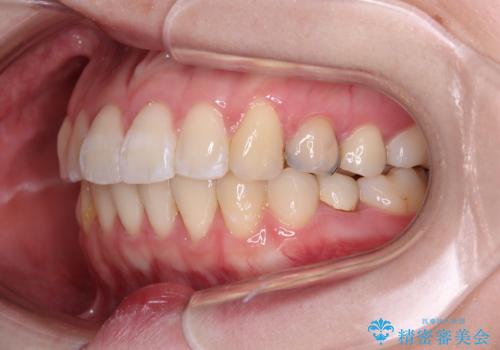

開咬と前方に飛び出した前歯 インビザラインによる矯正治療

- 上下前歯の非接触と叢生を気にして来院された患者様です。

開咬の改善はインビザラインの最も得意とするところであるため、インビザラインを用いて矯正治療を行うこととしました。

舌の突出癖改善のトレーニングをしっかりと行っていただき、上下前歯が接触する咬み合わせを達成することができました。